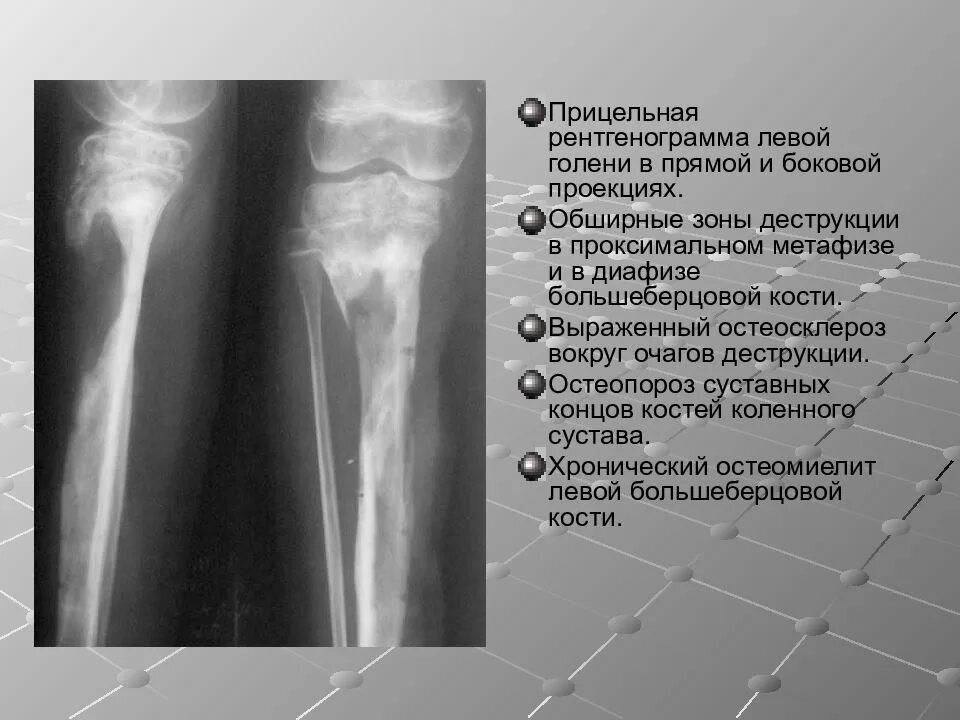

Участки остеосклероза в костях